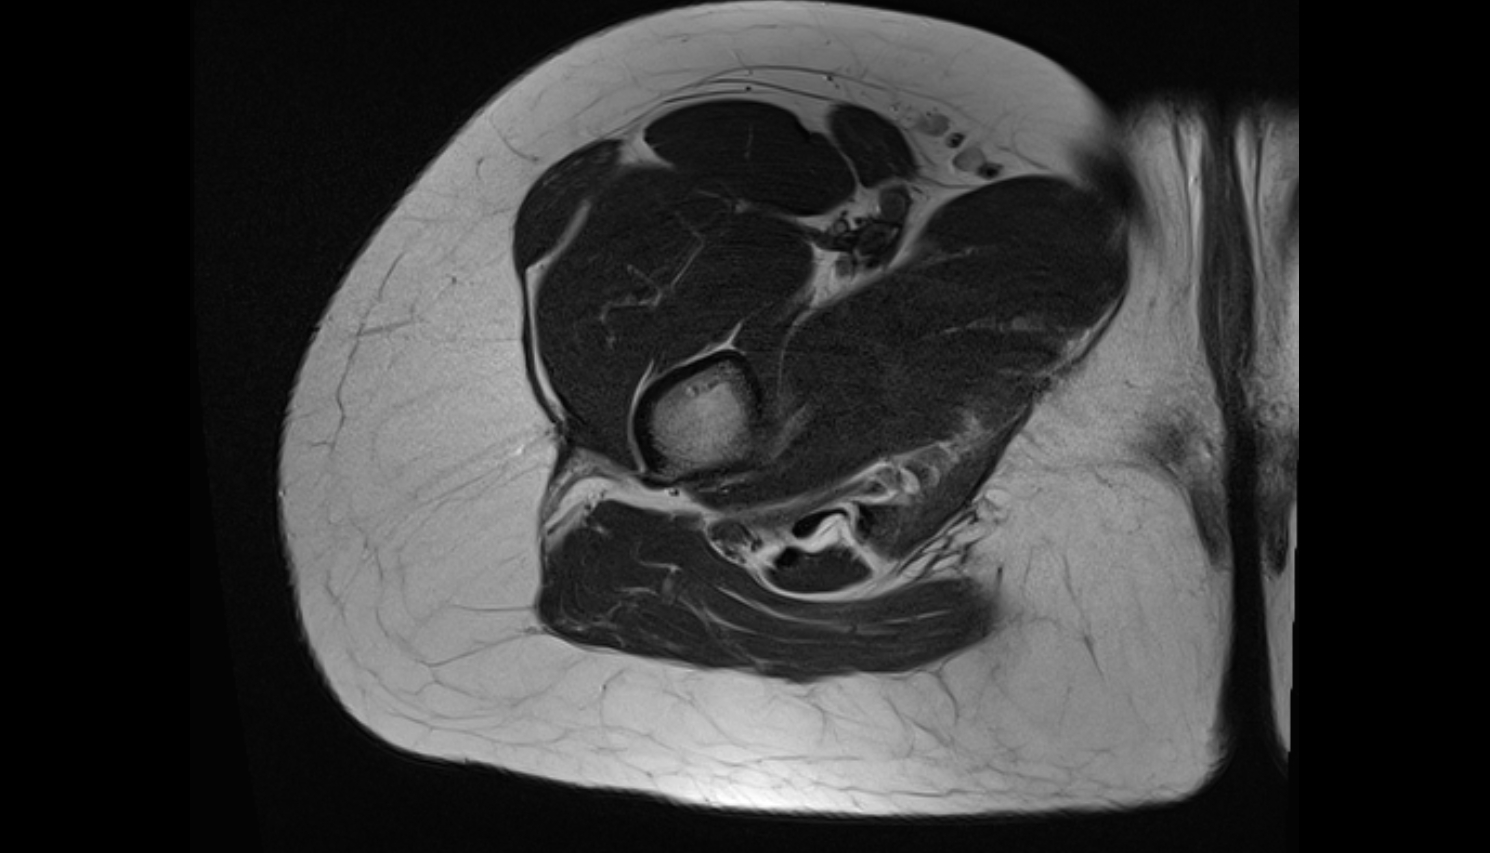

- Seminal vesicle

- Peripheral zone of prostate

- Anterior Fibromuscular Stroma of prostate

- Central zone of prostate

- Transitional zone of prostate

- Membranous urethra

- Prostatic urethra

- Penile urethra

- Rectoprostatic fascia (Denonvilliers' fascia)

- Rectosacral fascia (Waldeyer's fascia)

- Presacral fascia

- Fascia of pelvic diaphragm

- Rectal proper fascia (Fascia propria of the rectum)